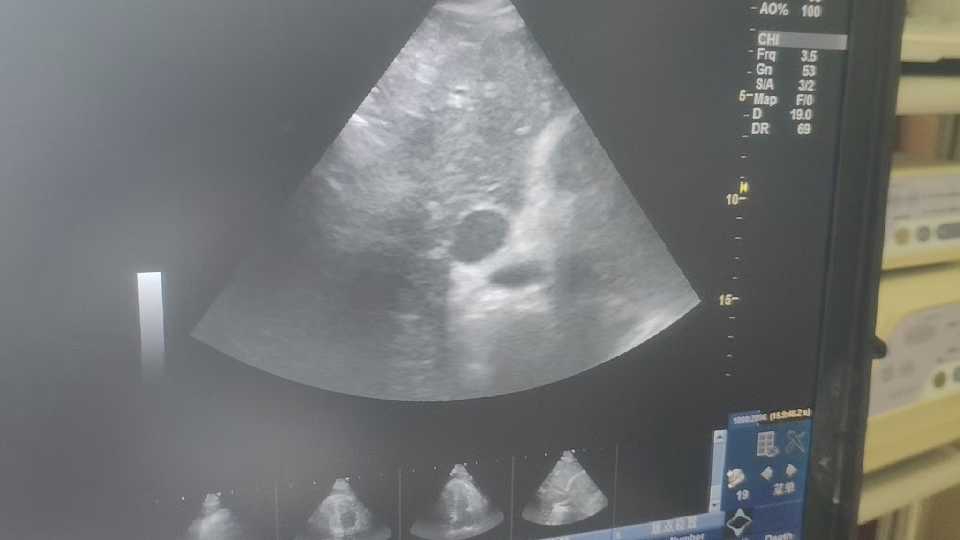

患者主动脉夹层,如厕后突发意识丧失,心跳骤停。抢救时床旁心脏彩超结果如下

经积极抢救,意识,心跳,呼吸未能恢复